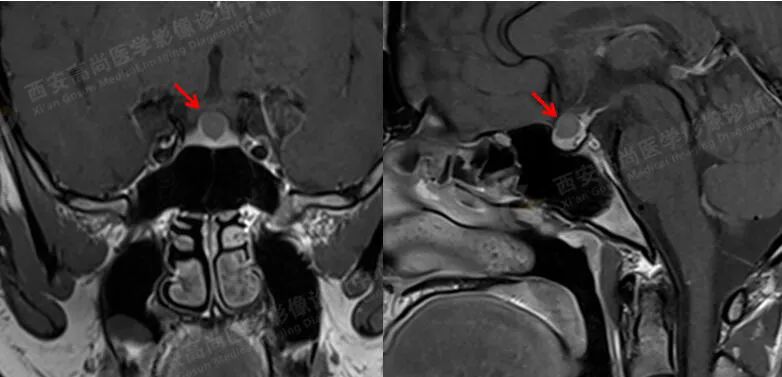

MRI 增强:垂体增大,最大高度约 1.1 cm,左右侧较对称,延迟期垂体前后叶之间中央区见大小约 0.8 cmX0.5 cm 的椭圆形低信号,边缘清晰。

诊断:垂体前后叶之间中央区椭圆形病灶,考虑 Rathke 囊肿。